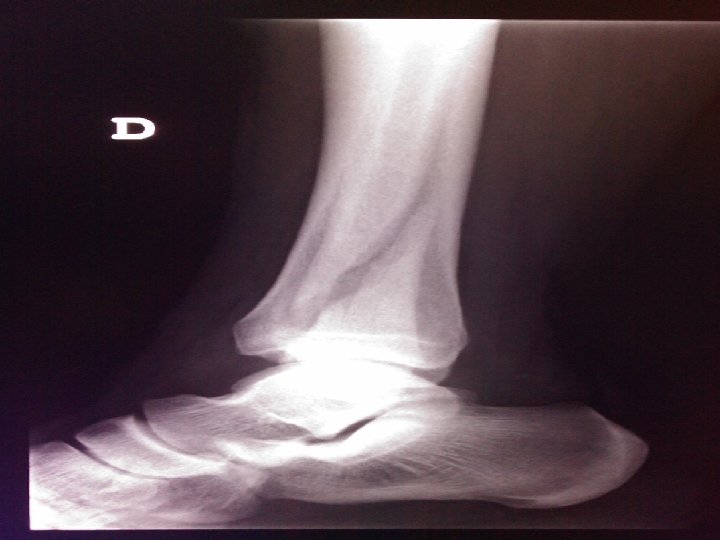

Caso clínico nº 1 • Varón de 29 años de edad • Dolor en tobillo dcho. tras sufrir torsión casual • No alergias a medicamentos • No antecedentes médicos de interés • IQ: Septoplastia • No Tto habitual • Marinero

EXPLORACIÓN: Tobillo dcho. Dolor, deformidad e impotencia funcional en cara lateral Erosión en cara medial

Pruebas complementarias Deben realizarse radiografías por lo menos en tres planos • A-P, eje perpendicular al plano de la placa • Lateral, eje paralelo al plano de la placa • Oblícua, eje en rotación interna, en un ángulo de 20º con respecto a la placa (proyección de mortaja) para valorar la congruencia articular

Juicio Diagnóstico: Fractura desplazada trans suprasindesmal maleolo peroné dcho.